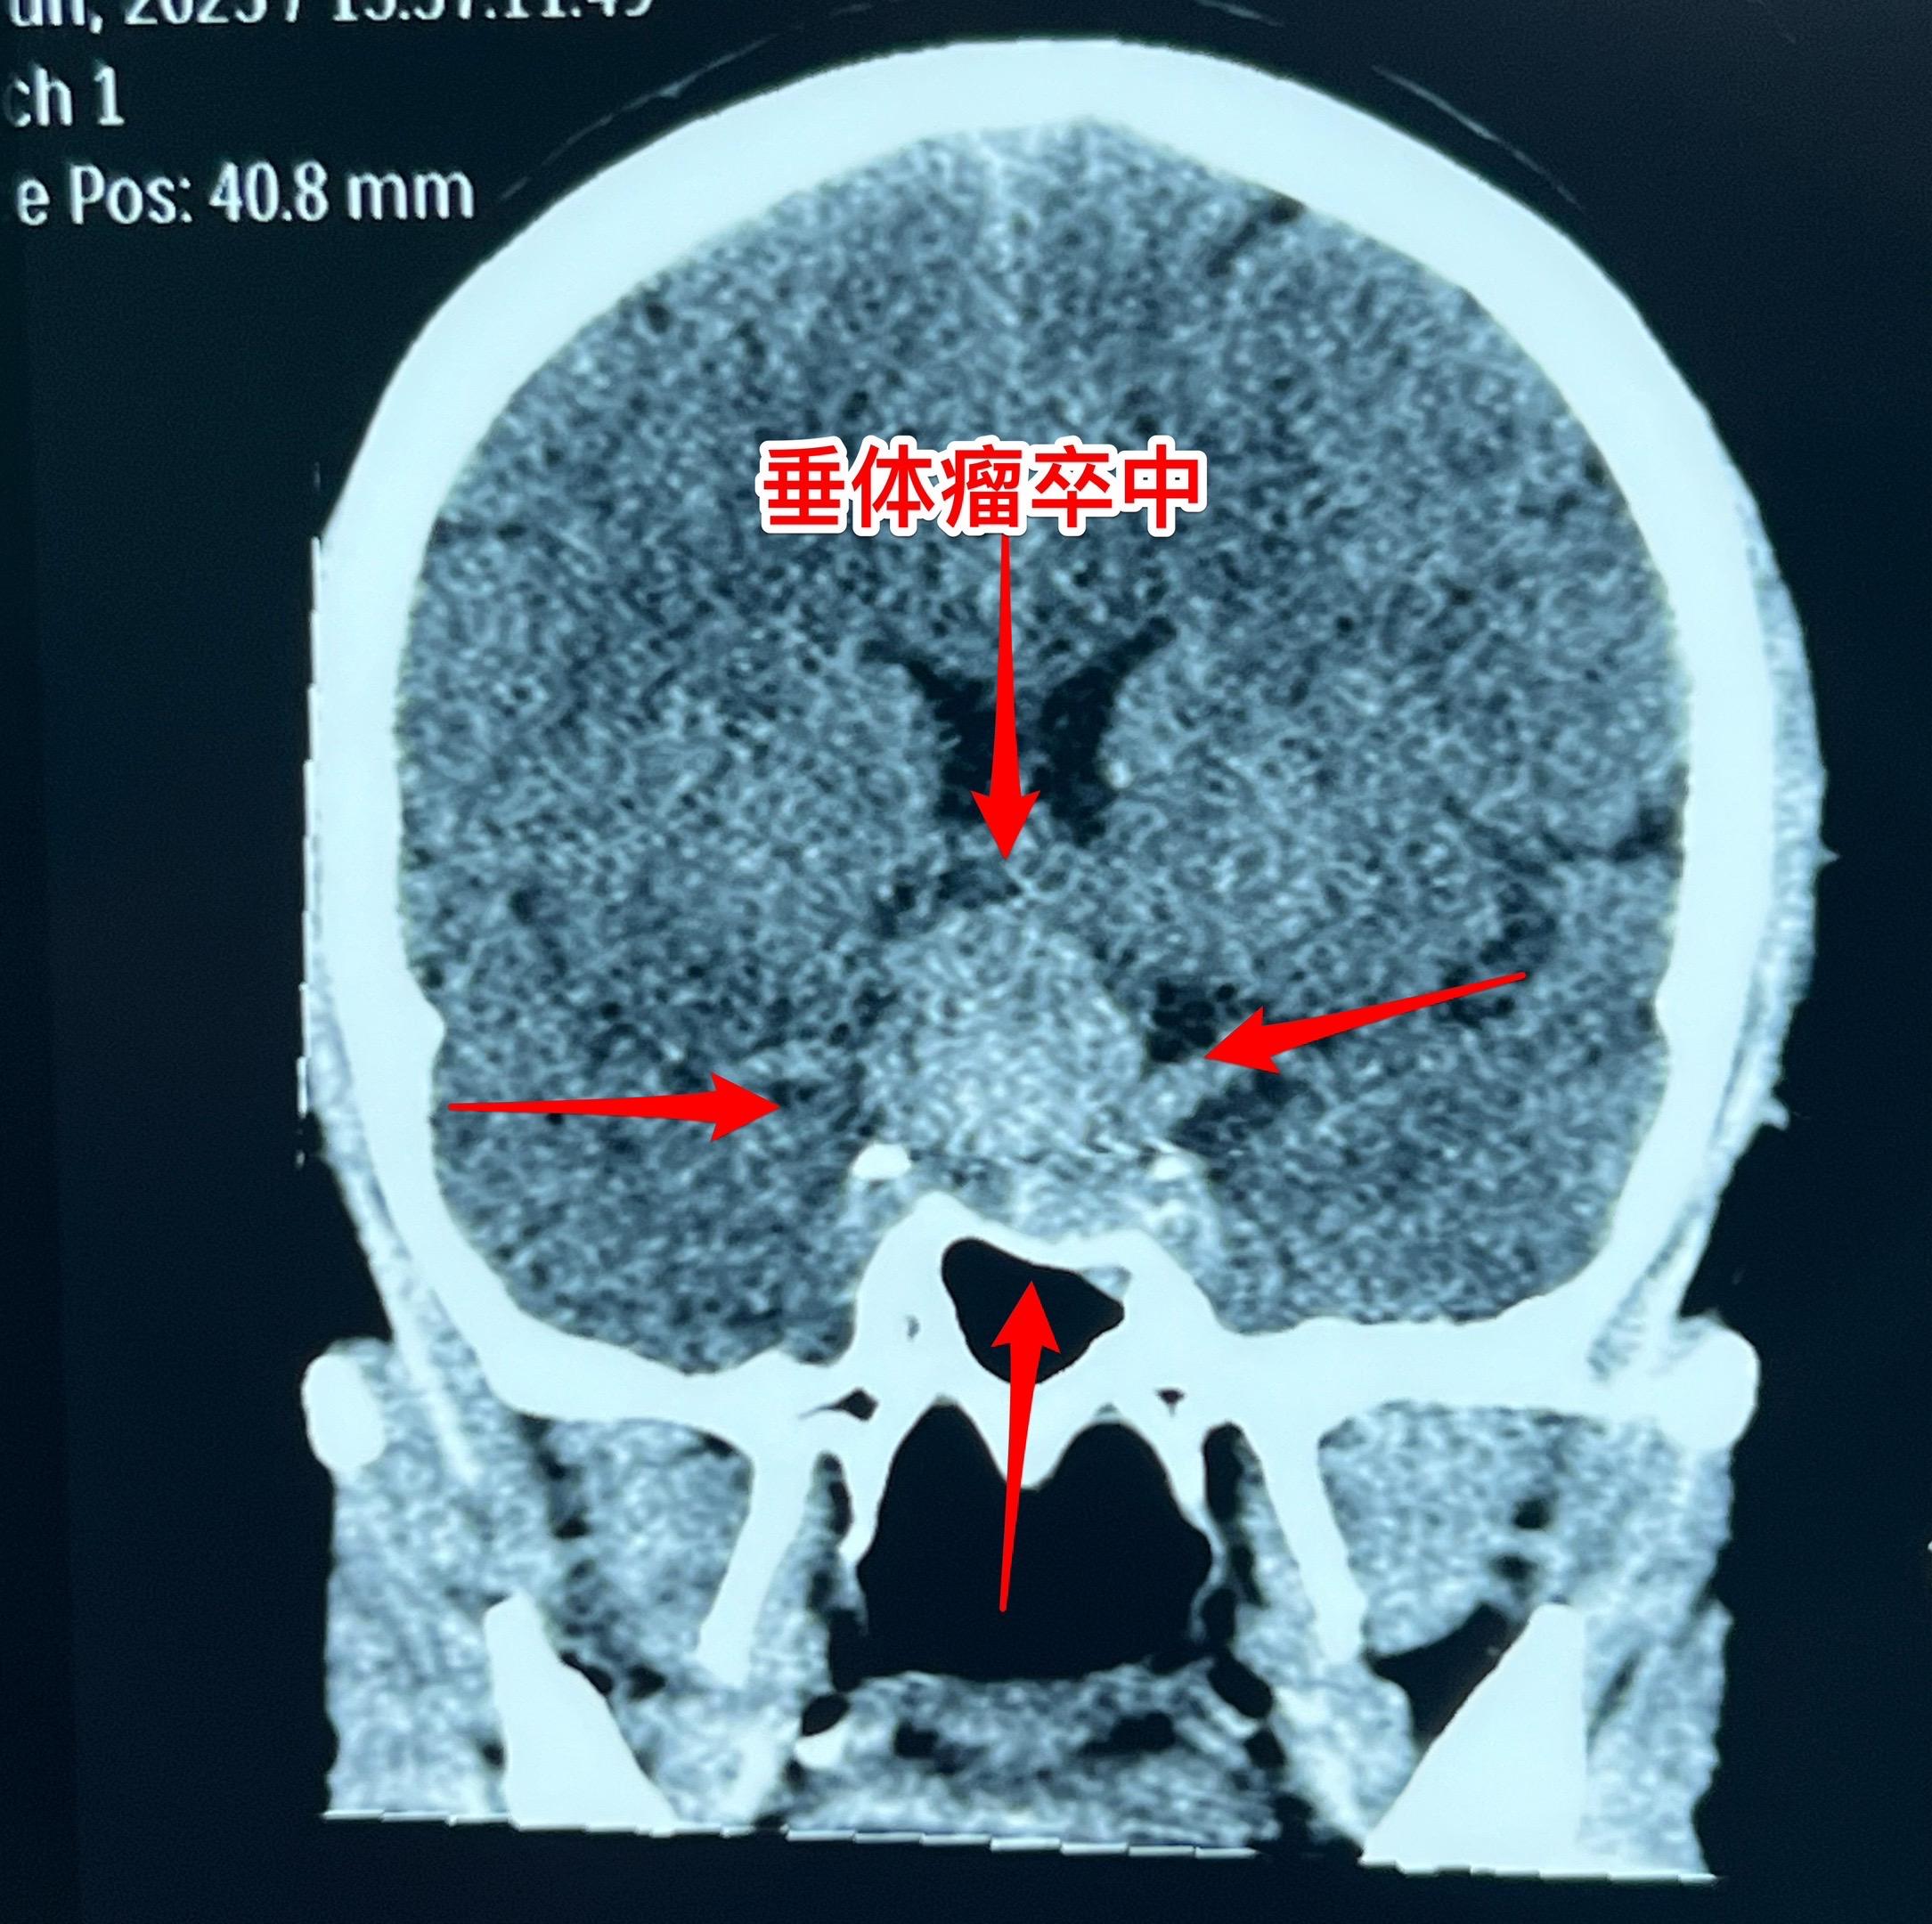

垂体瘤卒中,女教师6月12日突发视力下降。48岁定州市女教师6月12日早晨起床时尚无不适,上午出现眼前发花、白一块黑一块,随后双眼视力下降,几乎失明。 到当地医院行头部CT检查发现鞍区出血了,怀疑是动脉瘤破裂,随后作了磁共振、MRA检查,排除了动脉瘤破裂,诊断为垂体瘤卒中。 6月13日上午患者一家人自驾车出发,中午到了三博脑科医院。下午急诊行经鼻手术切除垂体瘤。 时间紧迫,极力挽救视力。 6月14日早晨患者自述视力有好转。